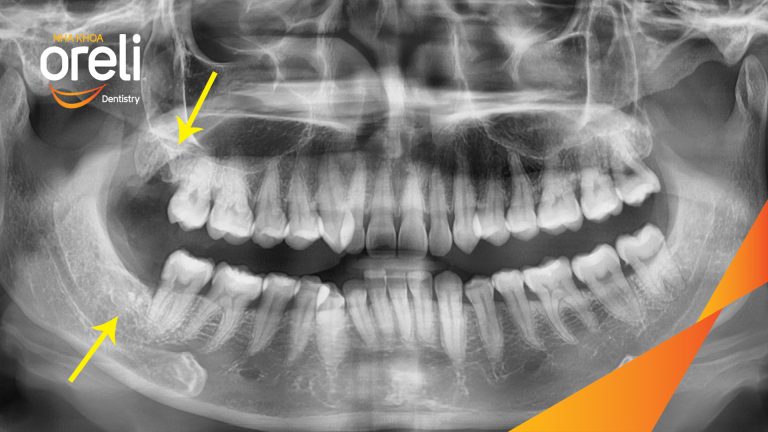

Nhổ răng khôn hai hàm do chen chúc – Ca thực tế tại Oreli

Nhổ răng khôn

Mọc lệch